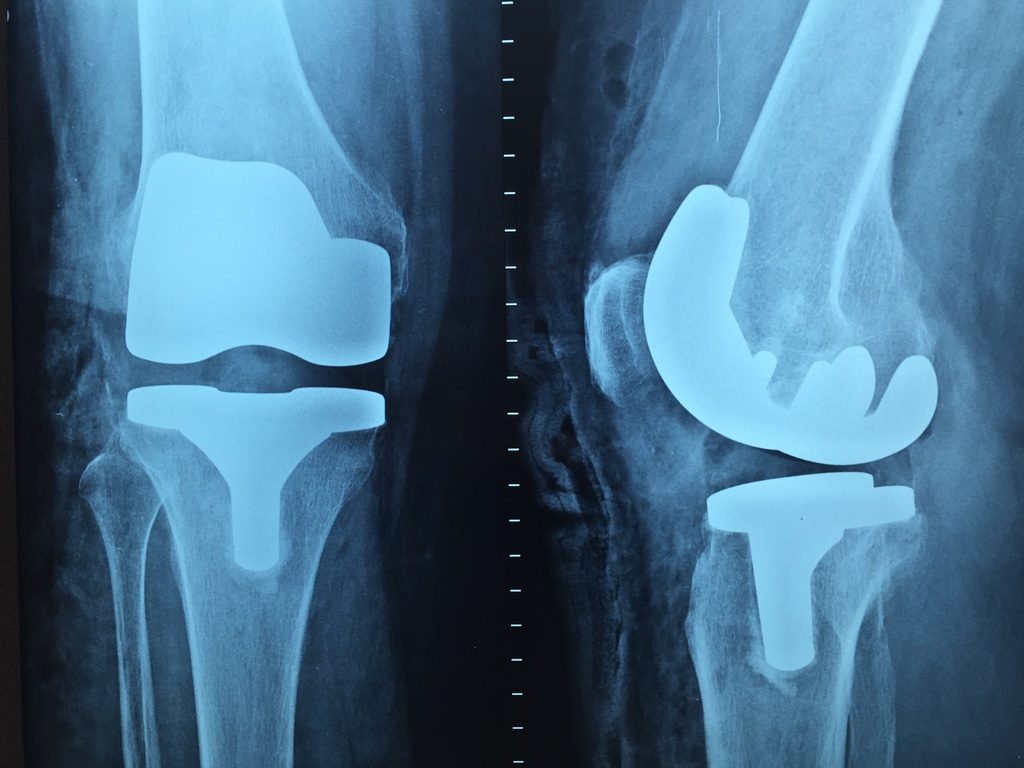

- มีการผิดรูปของข้อเข่า ซึ่งเกิดจากผิวข้อ (Cartilage) บางลงแล้วตัวของกระดูกมีการเสียดสีกันจนเกิดกระดูกงอก ทำให้เข่าผิดรูปและขยายซึ่งพบว่าผู้ที่มีเข่าเสื่อมอย่างรุนแรง รอบข้อเข่าจะใหญ่ขึ้น